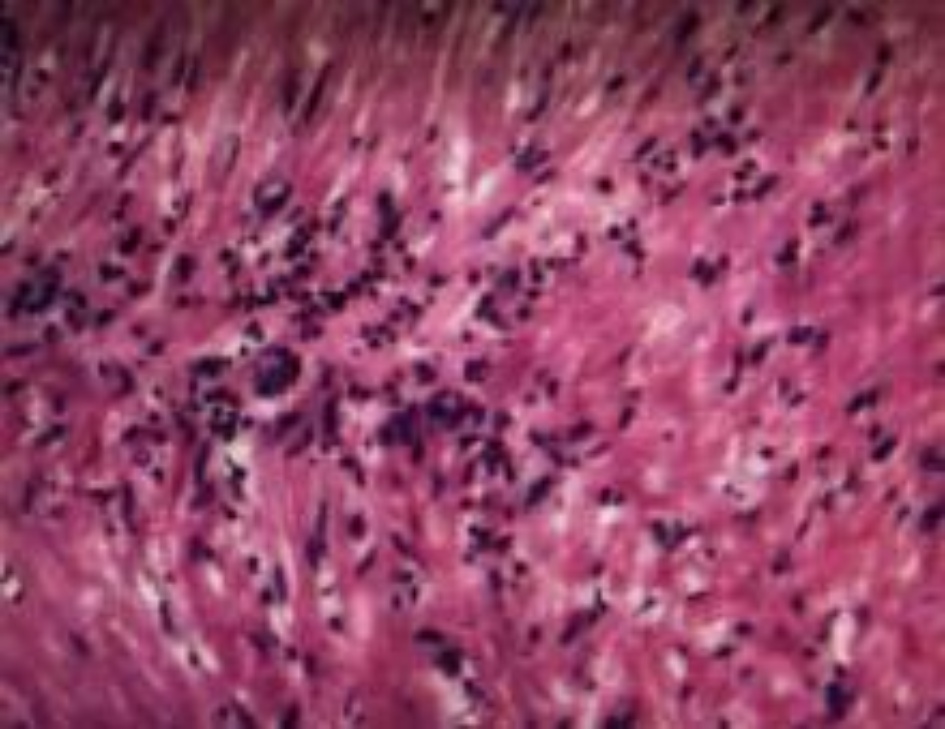

入院后2025年2月7日行胸部CT增强扫描检查提示:胸廓对称,纵隔气管居中。双肺纹理增多,右主支气管内见结节状高密度灶,边缘清楚,直径约1.1 cm,增强扫描两期CT值分别为31 Hu、63 Hu,强化程度不均匀;余段及段以上支气管通畅;双肺见少许索条影。双肺见多个直径小于5 mm实性小结节影。双肺门不大。纵隔内未见明显增大淋巴结。双侧胸腔未见积液。双侧胸膜未见增厚(见图1)。于2025年2月7日在全麻下行电子支气管镜检查示右主远端近上叶开口处可见一新生物堵塞管腔(见图2)。新生物予以径向超声探查,未见明显血管征象,予以电圈套器套取新生物,予以电切切除,右主远端支气管通畅。结束退镜;过程顺利,患者无不良反应;检查结束后患者心率70次/分,血氧饱和度98%,血压110/70 mmhg安返复苏室。常规病理活检肉眼见:右主支气管内新生物:灰白色组织1块,大小约1.5 × 1.3 × 0.6 cm,切面灰白色,质稍韧。病理诊断:(右主支气管内新生物)平滑肌瘤(见图3)。免疫组化结果:瘤细胞示SMA (+),Desmin (+),CD34 (−),HMB45 (−),H-Caldesmon (+),CD117 (−),Melan A (−),Ki67 (+)约1%。结合形态学特点和免疫组化检查,病理诊断为原发性支气管平滑肌瘤。于2025年2月9日好转出院。术后3月对患者进行电话随访,诉当地医院复查胸部CT未见肿瘤复发,一般状况良好。

Figure 3. Histopathological examination (H&E staining, 200×) of the endobronchial neoplasm shows fascicles of spindle-shaped smooth muscle cells consistent with leiomyoma

3. 该支气管内肿瘤的组织病理学检查(苏木精–伊红染色,200×)显示梭形平滑肌细胞呈束状排列,符合平滑肌瘤表现

该病患者的支气管镜检查可直接观察肿瘤的位置、大小、形态及表面特征(如是否光滑,有无出血等)。通过支气管镜获取肿瘤组织进行病理学活检,以明确组织学诊断[7]。文献报道原发性支气管平滑肌瘤的瘤体多为宽基底,个别有短蒂,瘤体表面富有新生的血管,质地较韧,大体病理特征呈淡粉色或灰白色,表面光滑,组织病理学特征表现为:肿瘤由分化良好的平滑肌细胞组成,细胞核呈梭形,排列成束状,无核分裂象或细胞异型性,可与平滑肌肉瘤鉴别[8]